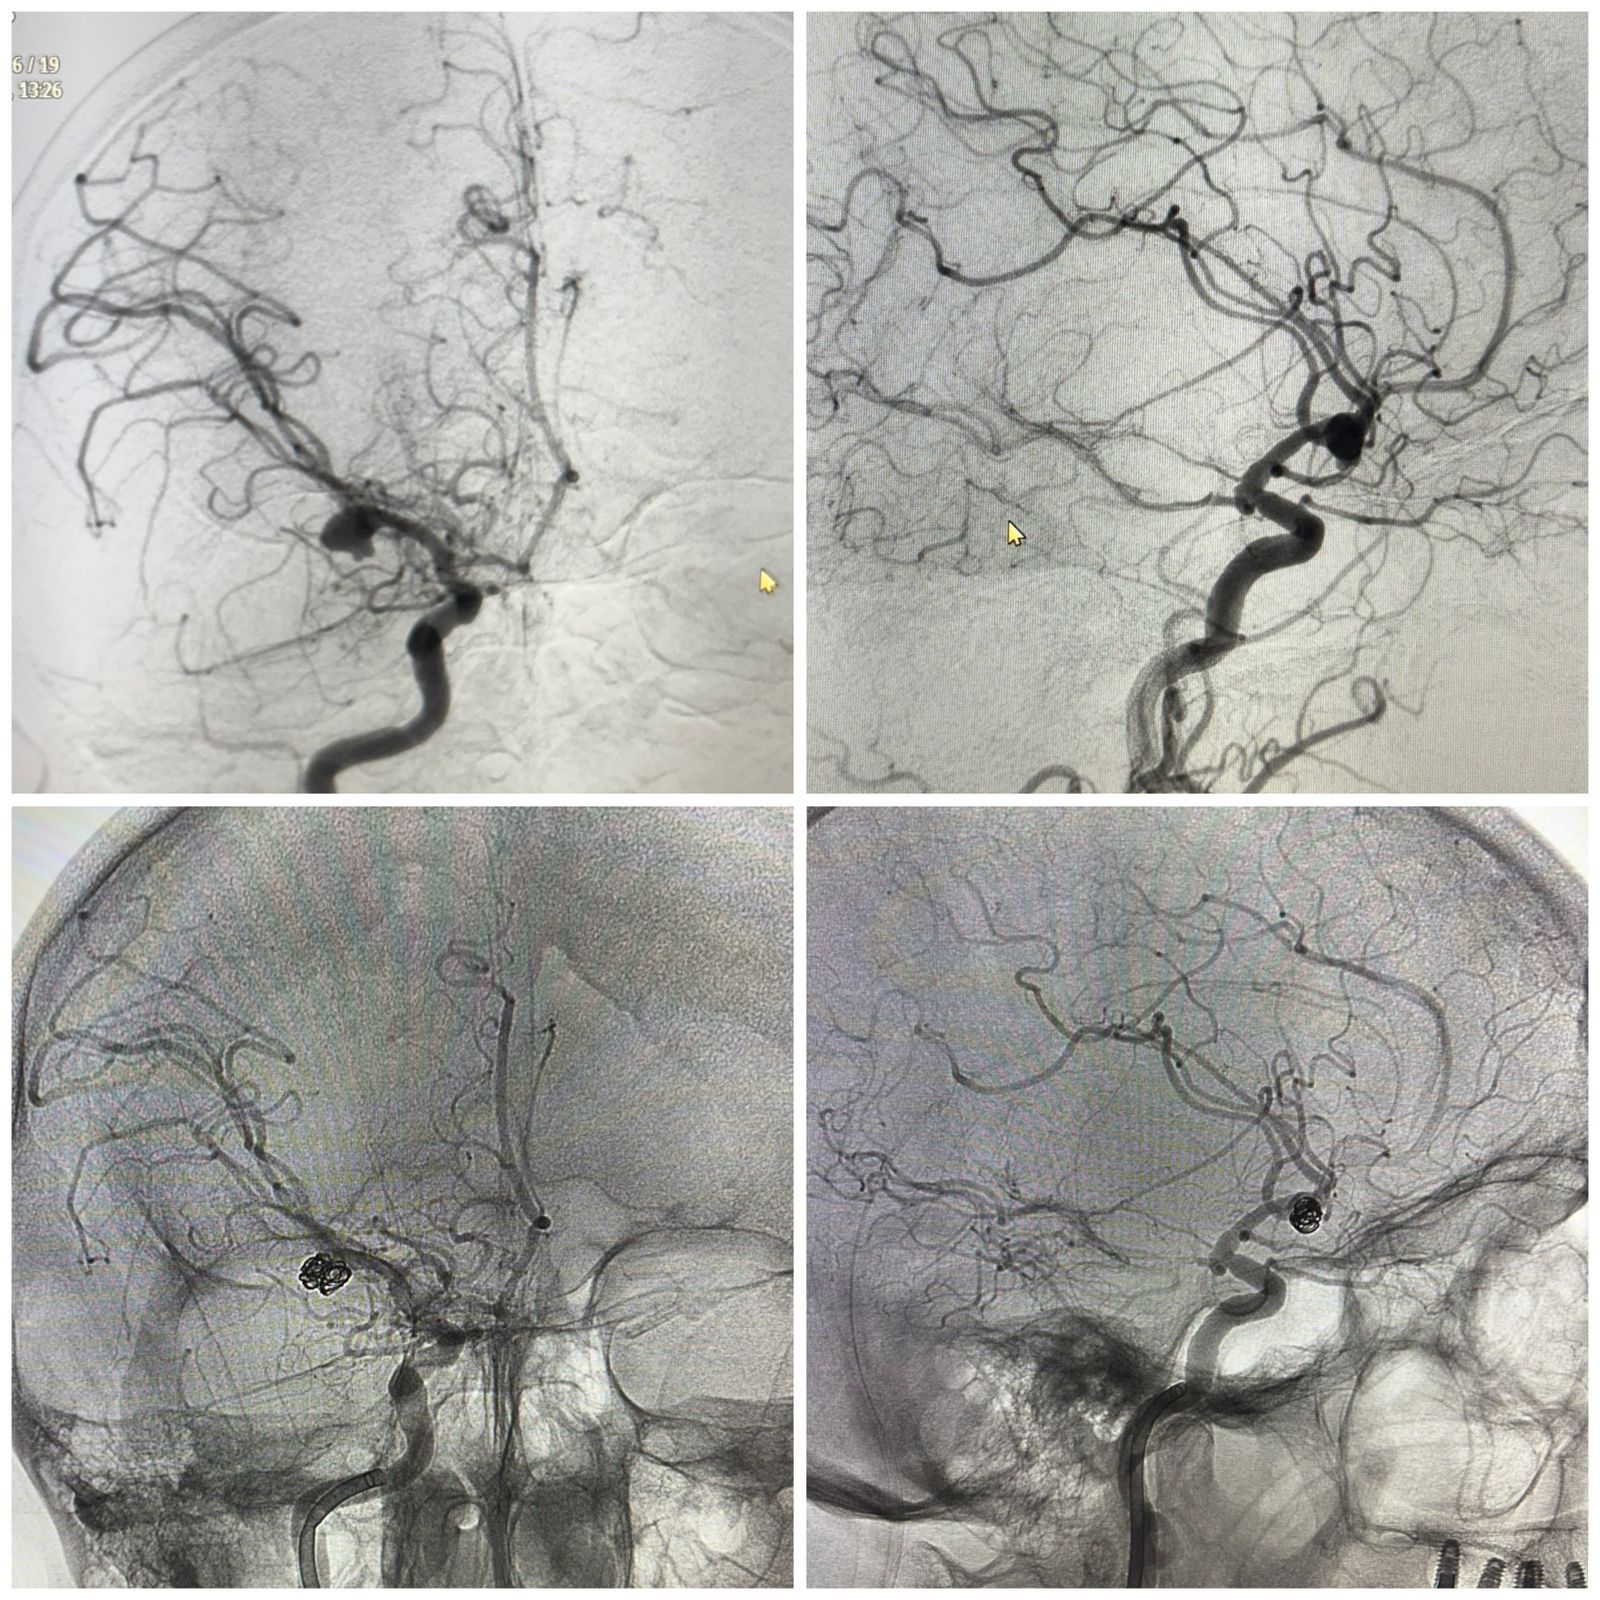

«Ми құрылымдарының қысылу қаупі аса жоғары болғанын ескере отырып, пациентке үш отаны қатарынан жасау қажет болды. Біріншісі – жарылған аневризманы эндоваскулярлық эмболизациялау. Бұл – қанды тоқтатып, қайта жарылудың алдын алуға мүмкіндік беретін зақымы аз нейрохирургиялық әдіс. Екіншісі – сыртқы қарыншалық дренаж орнату. Оның мақсаты – басішілік қысымды төмендетіп, ми жұлыны сұйықтығының айналымын тұрақтандыру. Үшіншісі – ми ішіндегі гематоманы алып тастайтын декомпрессиялық ота. Бұл аса дәл микроскопиялық техниканы қажет ететін көлемді нейрохирургиялық араласу», дейді Алматы №4 қалалық клиникалық аурухана нейрохирургы Алдонгар Айсаутов.